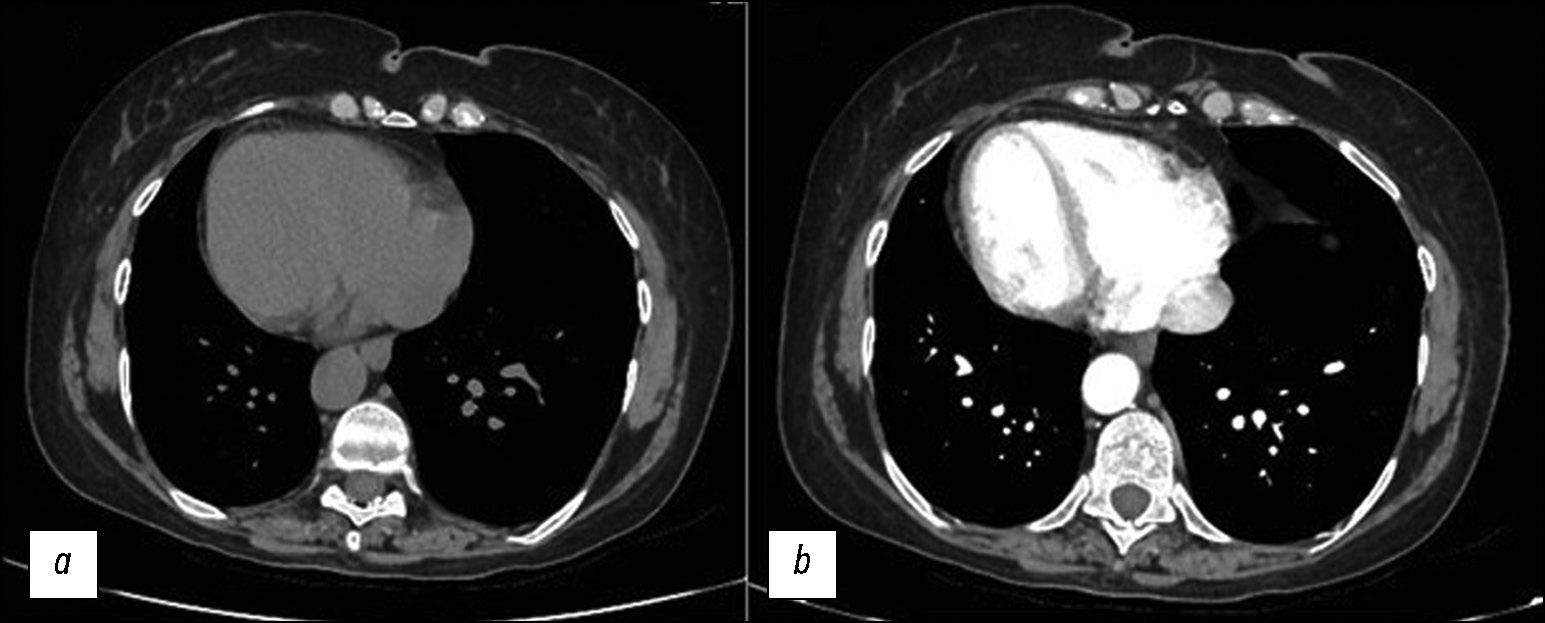

Prospective evaluation of the extensibility of the ascending aorta wall and its vascular prosthesis in a patient with an aneurysm with technically flawless surgical correction and postoperative decrease in functional parameters: A case report

Abstract

In this clinical case, a patient who had an instrumentally detected aneurysm with the lumen expanding up to 60 mm underwent a surgically flawless prosthetic replacement of the ascending aorta. This treatment led to decreased exercise tolerance, decreased contractile function of the left ventricular myocardium at rest, and enlarged pulmonary artery. The leading factor was a decrease in the volume of systolic expansion of the aorta down to 5 mL (at the initial 13 mL), despite a noticeable increase in the extensibility and a decrease in mechanical stiffness compared with initial indexes of the affected aortic wall. In the literature review, considering mechanical extensibility and elasticity, problems in creating aortic prostheses equivalent to those for healthy biological tissues were discussed.

342-353